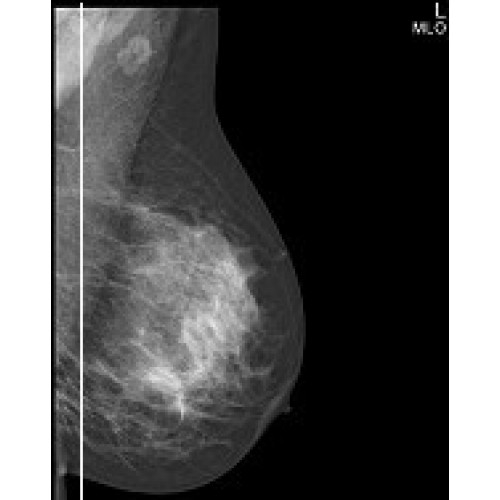

IMS GIOTTO IMAGE 3D

Современная маммографическая система с технологией томосинтеза для точной трехмерной визуализации. Обеспечивает высокое качество изображения при минимальной лучевой нагрузке. Подходит для скрининговых программ и углубленной диагностики. Интегрируется с медицинскими информационными системами.

Маммограф IMS GIOTTO IMAGE 3D – инновационная система для ранней диагностики заболеваний молочной железы с технологией томосинтеза. Аппарат сочетает высокое качество изображения с минимальной лучевой нагрузкой, что делает его идеальным решением для современных медицинских учреждений.

• Технология цифрового томосинтеза для трехмерной визуализации тканей

• Полноценная 2D и 3D маммография в одном исследовании

• Режим DBT (Digital Breast Tomosynthesis) для послойного анализа